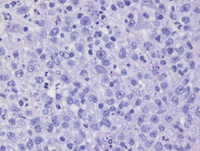

H&E images

The lymphoid material present demonstrates generalized effacement of the lymph node architecture. There is normal and capsular thickening and fibrosis with an associated atypical lymphoid infiltrate with multifocal geographic areas of necrosis. The atypical lymphoid infiltrate comprises scattered sheets of large lymphoid cells with occasional "Hallmark" cells and "lacunar-like" forms seen at places. These large cells are admixed with neutrophils, small lymphocytes and eosinophils with variable vascular proliferation in some areas. At places, there is intravascular infiltration by neoplastic cells.